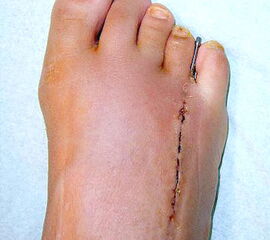

Das im Folgenden vorgestellte Operationsverfahren beschreibt die Kallusdistraktion von Metatarsalia nach den Prinzipien von Ilisarov 21 unter Verwendung eines internen, winkelstabilen Titan-Minifixateur (Klauser 2009). Der interne Distraktor ermöglicht während der Distraktions- und der Durchbauungsphase aufgrund seiner hohen Stabilität je nach Modell (18 mm, 23 mm) eine Verlängerung von bis zu 25 mm. Nach interner Anlage des Minifixateurs, meist lateral, kann über eine kontinuierliche Kallusdistraktion der Metatarsalebogen unter frühzeitiger Mobilisation im Gips oder Short-Walker rekonstruiert werden 15. Über einen interdigital und transcutan ausgeleiteten Aktivatorstab wird die Distraktion vom Patienten selber täglich morgens und abends durchgeführt. Zusätzlich vorliegende Strahlpathologien, wie zum Beispiel eine verkürzte Strecksehne oder ein kontraktes Metatarsophalangealgelenk können im Rahmen der Erstoperation ebenso therapiert werden wie z.B. ein Hallux valgus, ein Hallux valgus interphalangeus und/oder ein Digitus quintus varus (Klauser 2009). Nach Rekonstruktion des Metatarsalebogens wird in einem zweiten, kleinen Eingriff der Aktivatorstab über eine Spezialpinzette diskonnektiert und entfernt, wobei der Distraktor als interne Fixation belassen wird. Die Entfernung des Distraktors erfolgt in der Regel nach 9 – 12 Monaten, da es sich meist um angeborene kindliche Fehlbildungen handelt (Brachymetatarsie) und eine operative Intervention frühzeitig im Kindesalter erfolgen sollte (Klauser 2009).

• Erster Eingriff: Implantation des internen Distraktors, Osteotomie des verkürzten Metatarsaleknochens, ggf. Strecksehnenverlängerung, Grundgelenkrelease und dorsale Kapsulotomie.

• Zweiter Eingriff: Diskonnektieren des transcutan ausgeleiteten Aktivator, falls möglich, über eine kleine Inzision von 1,5 bis 2 cm, in der Regel jedoch über Eröffnen der alten Schnittführung mit ggf. Strecksehnenverlängerung und erneutem Grundgelenk-Release sowie ggf. Ausleiten einer Penroselasche oder einer Gentamycin-Palacos-Minikette.